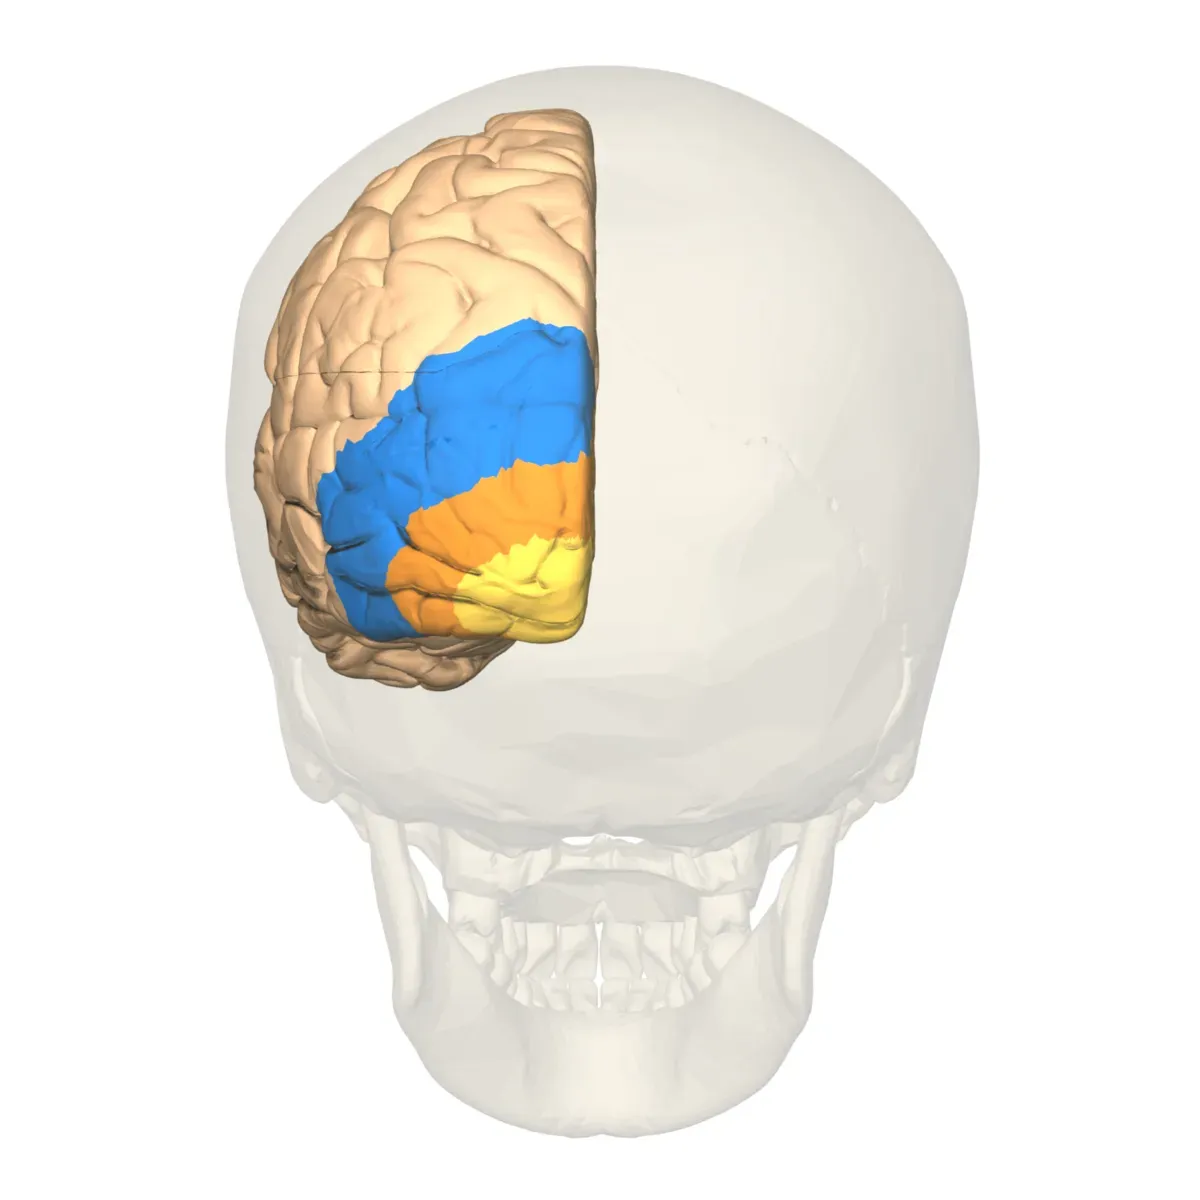

Neural Correlates Point to Posterior Brain Regions

For years, neuroscientists have been hunting for the physical substrate of consciousness in the brain. Recent findings showing that the anatomical neural correlates of consciousness are primarily localized to a posterior cortical hot zone that includes sensory areas, rather than to a fronto-parietal network involved in task monitoring and reporting. This challenges older ideas that consciousness depends heavily on frontal brain regions involved in planning and executive control.

Here’s the thing: the back of your brain, where visual and sensory processing happens, seems more crucial to generating conscious experience than the front regions involved in complex thinking. Lateral and ventral occipitotemporal activity has been shown to correlate with visual consciousness, including in no-report conditions. That finding holds even when people aren’t reporting what they experience, suggesting these areas aren’t just involved in communication but in consciousness itself.